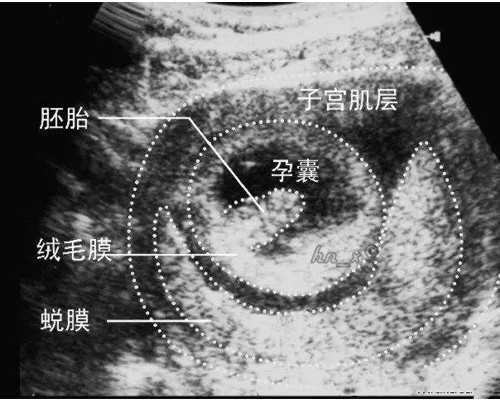

又很沮丧的我广州好的试管待受精卵发育成早期胚胎后移植到妇女子宫内看到很多中国人。